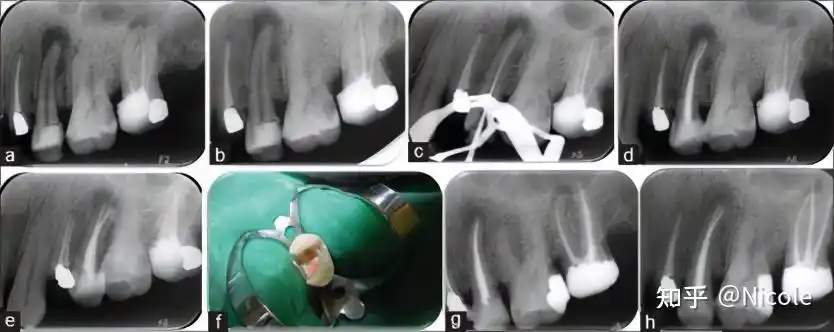

上颌第二磨牙双生牙的根管治疗病例报告1

第二磨牙残根橡皮障下rct现代根管治疗培训后的改进